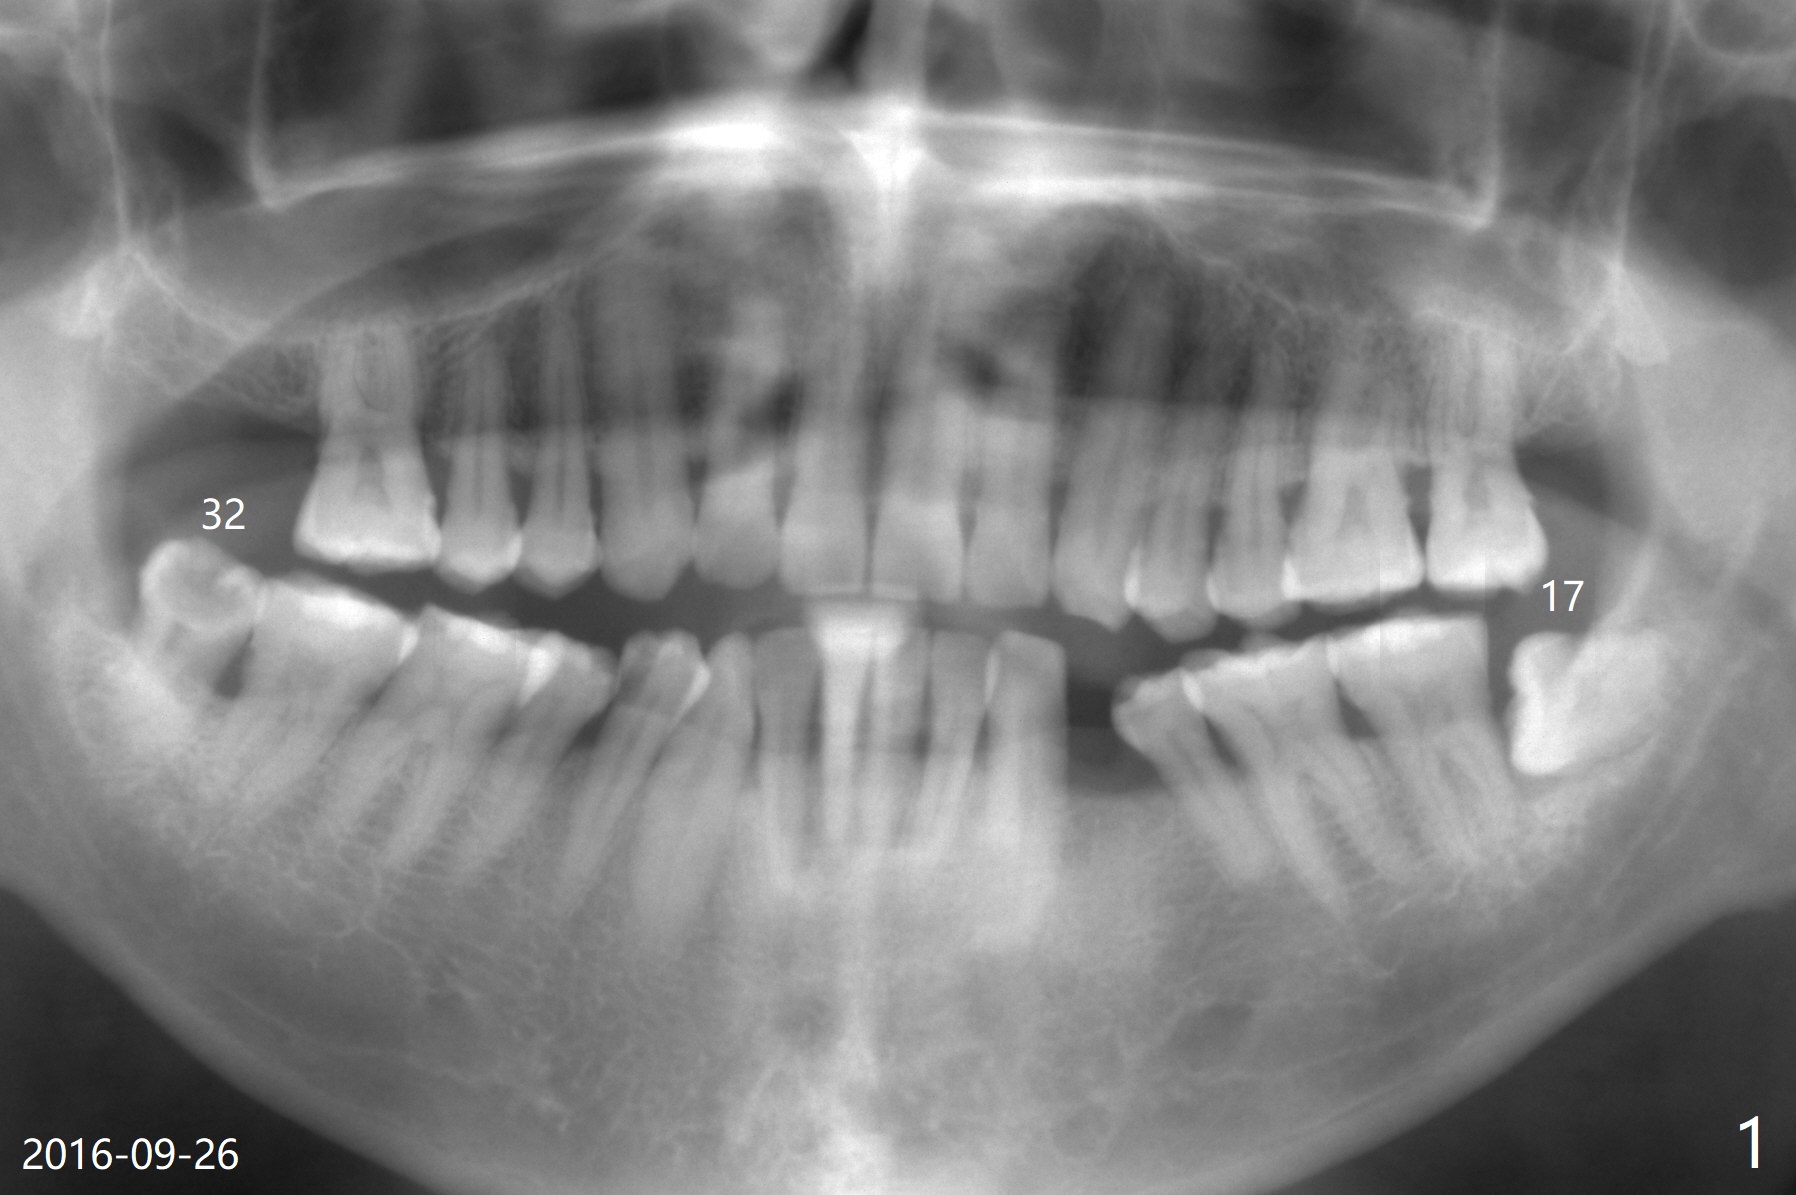

A 51-year-old man returns for #17 extraction 3.5 years post #32 one (Fig.1,2). The bone distal to #18 is lost severely (Fig.1). After #17 extraction and granu-lation tissue removal, Collagen Plug (Fig.3 C), Osteogen Plug (O) and cortical: cancellous (50: 50) mine-ralized allograft (.5-1 mm) saturated with ~ .2 ml of .3 mg/ml of rhPDGF-BB (B, one component of GEM21S) is placed in the socket. The patient returns with chief complaint of referring pain to the left ear 6 days postop, although the extraction wound looks fine. The mild pain (controlled by pain medication) persists 10 days and 1 month postop. The pain 1 month postop is associated with mastication. It appears that the tooth #18 is periodontally compromised. Occlusal equilibrium is required.